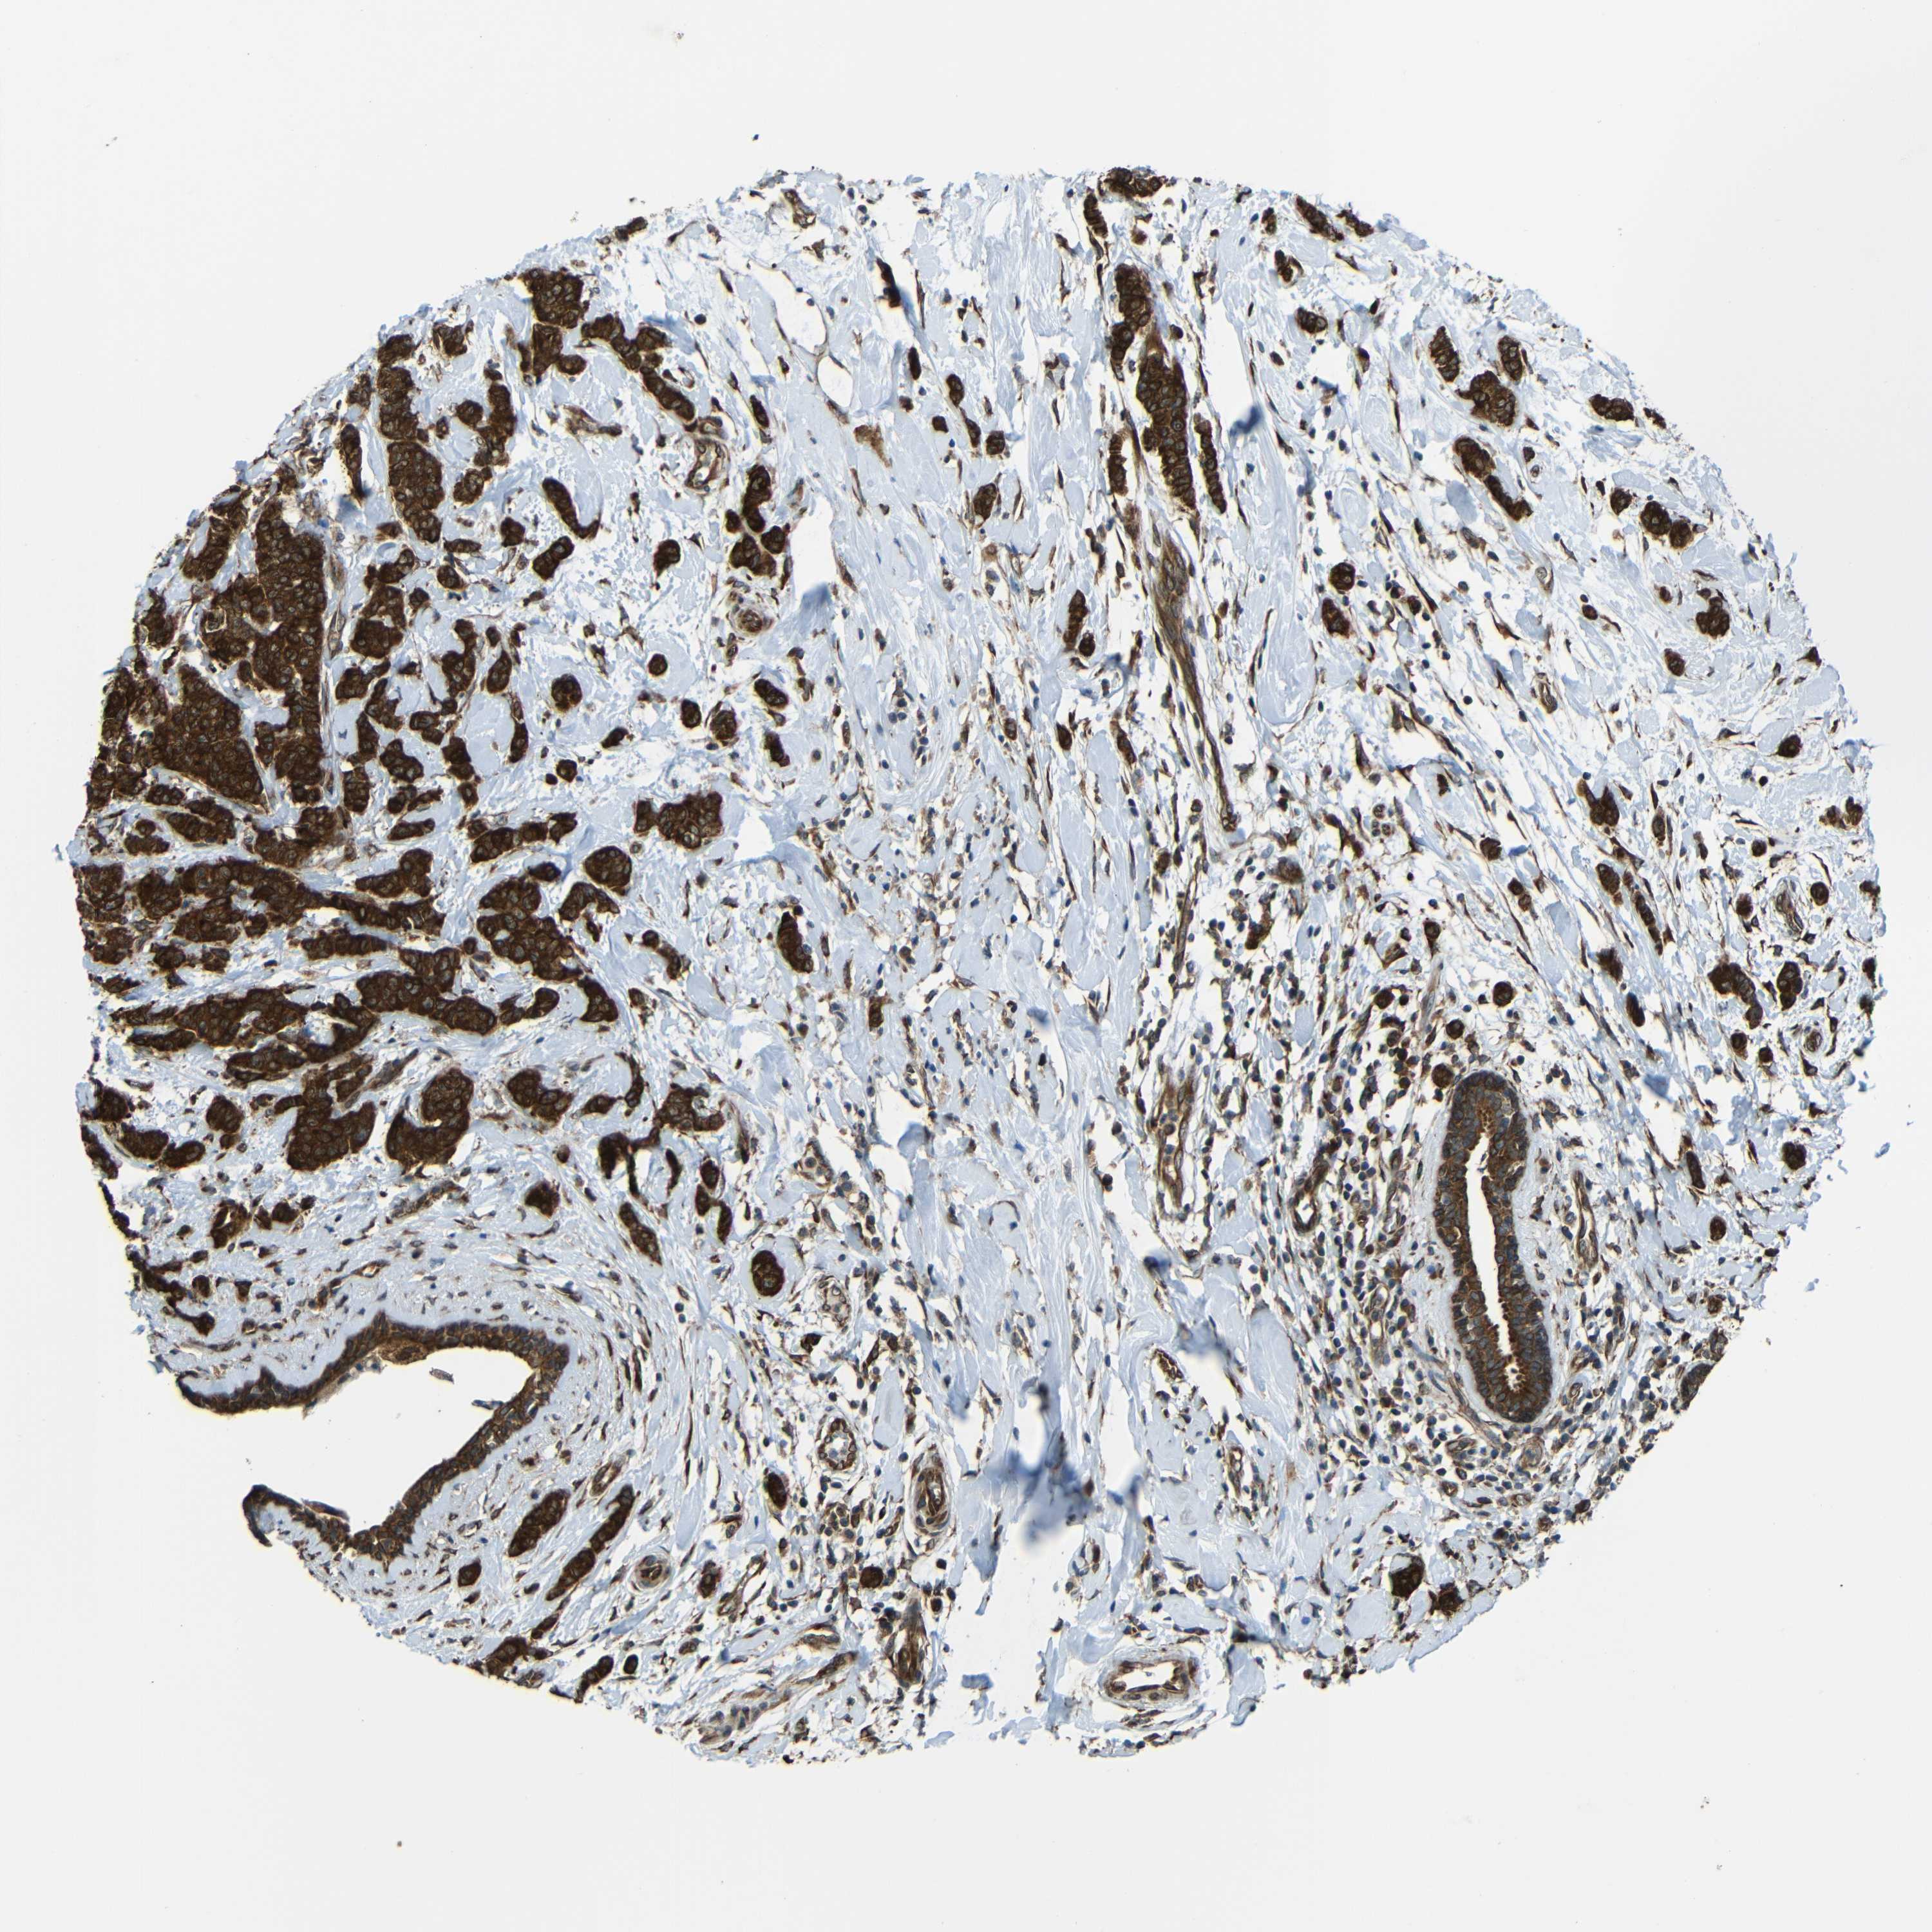

CANCER BREAST CANCER Show tissue menu

BRCA TCGA BRCA VALIDATION PROTEIN EXPRESSION

VAPB is potential prognostic, high expression is unfavorable in Breast Invasive Carcinoma (TCGA)